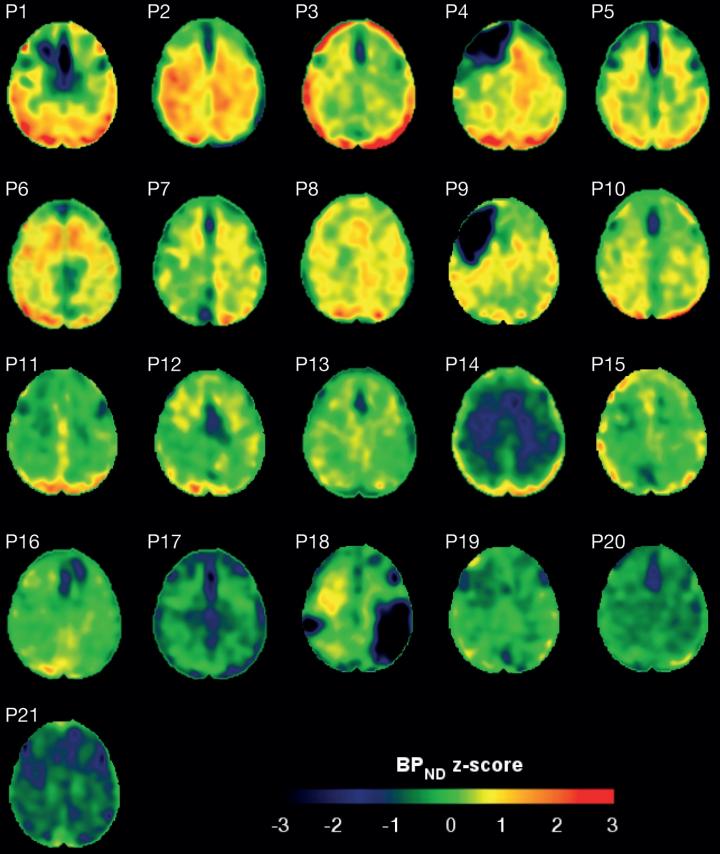

image: These scans show the amount of tau protein in the brains of patients who have suffered a traumatic brain injury. Red represents increased tau accumulation.

The study used a type of brain scan, called a PET scan, combined with a substance that binds to tau protein, called flortaucipir, to study the amount of tau protein in the brains of head injury patients.

The results revealed that, collectively, patients with head injury were more likely to have tau tangles. The paper also showed that patients with tau tangles had higher levels of nerve damage, particular in the white matter of the brain. None of the healthy individuals had tau tangles.